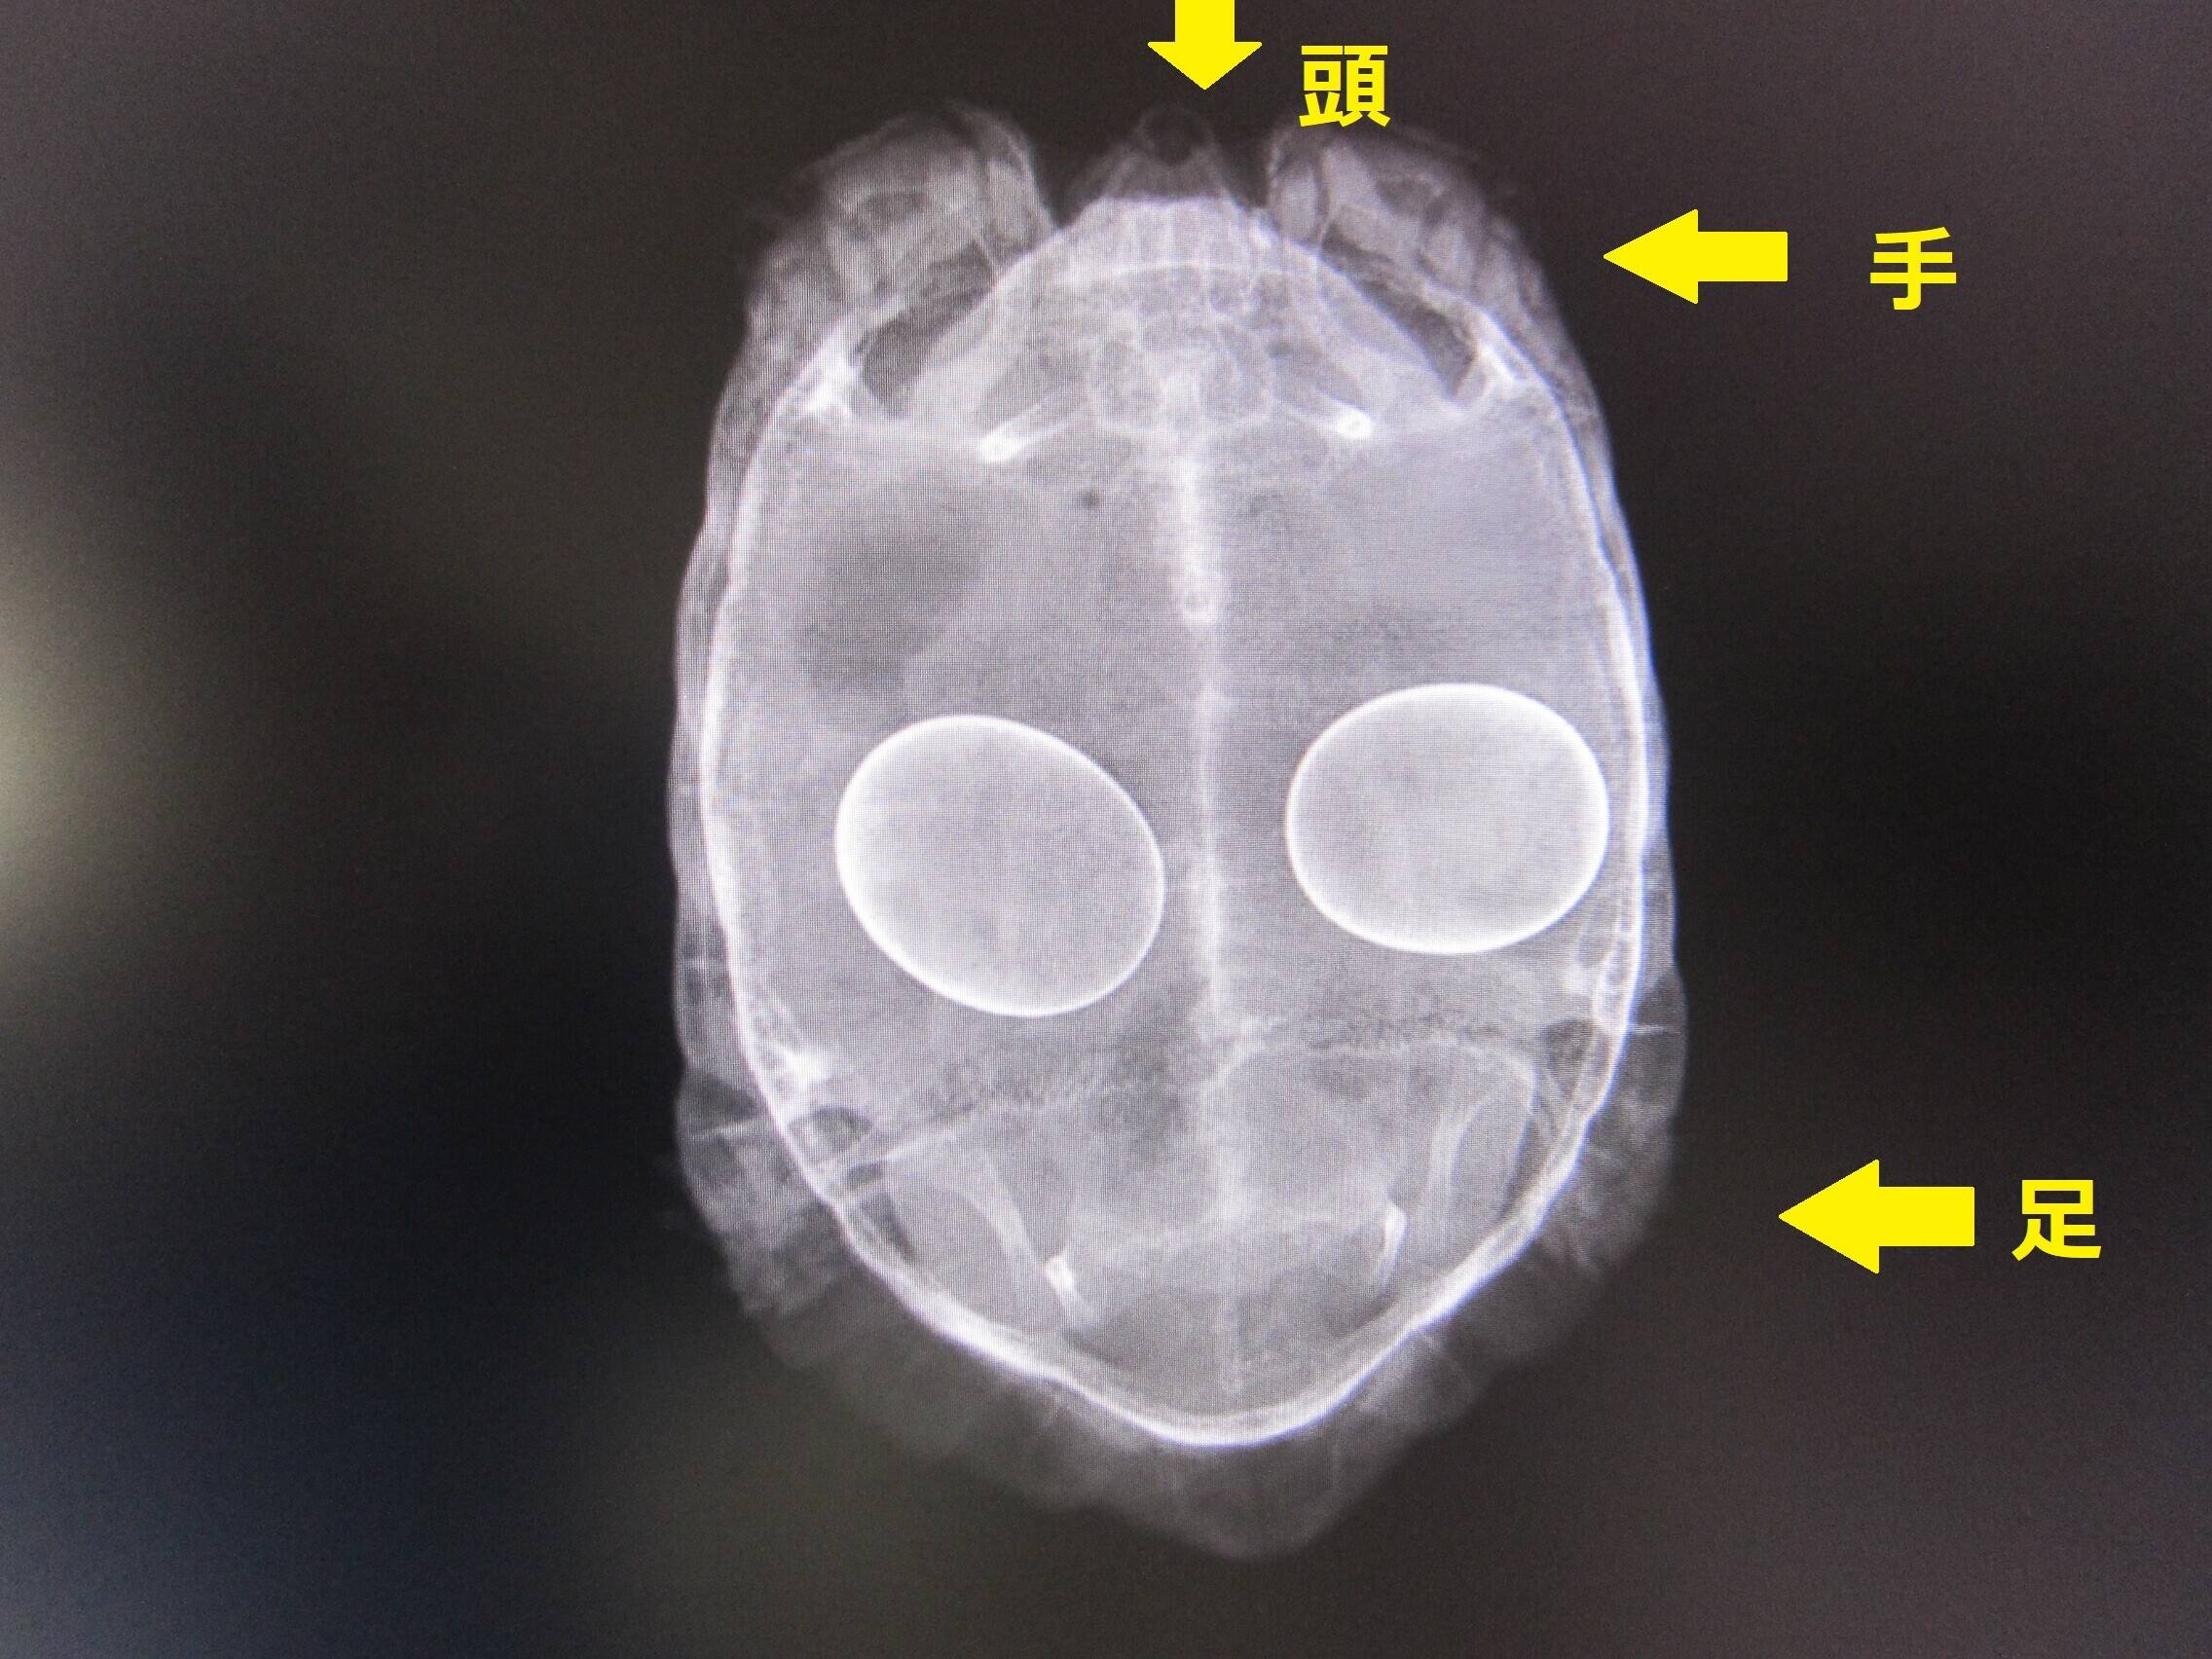

まずは、コチラ。

ウルトラマン!?

なわけなく、よーく見ると・・・

頭と手がありますね。もちろん足も。

そう、カメですよね!

どのカメかというと、コチラ。

はい、エジプトリクガメでした。

この個体は以前お腹に卵を持ったまま、ずっと産まなかったため、手術で卵を取り出したのです。

その後元気になり、現在も爬虫類館で展示されています。